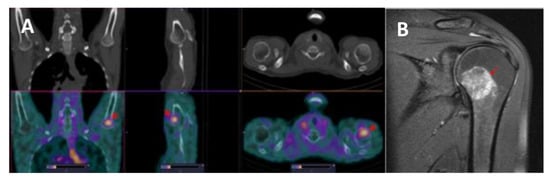

3.3. [99mTc]Tc-TG SPECT/CT Imaging of Nodal and Extranodal Lesions